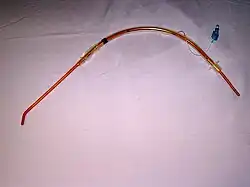

Bougie ou mandrin d'Eschmann

Il s'agit d'une longue tige de plastique relativement rigide dont le bout (environ 2 cm) forme un léger angle. La tige est insérée lors d'une laryngoscopie. Le bout de la tige est pointé vers le haut. La friction du bout de la tige sur les anneaux trachéaux permet de savoir que celle-ci est en bonne position sans visualiser la glotte. La sonde d'intubation est alors enfilée sur le mandrin et glissée jusque dans la trachée, la laryngoscopie étant maintenue pour soulever l'épiglotte. Le Mandrin d'Eschmann est ensuite retiré et la sonde raccordée au circuit respiratoire.

Sonde d'intubation trachéale avec ballonnet gonflé (seringue de gonflage en place). Mandrin d'Eschmann pour intubation difficile.

Mandrin d'Eschmann pour intubation difficile. Ballon d'anesthésie avec filtre antibacterien monté sur une sonde d'intubation.